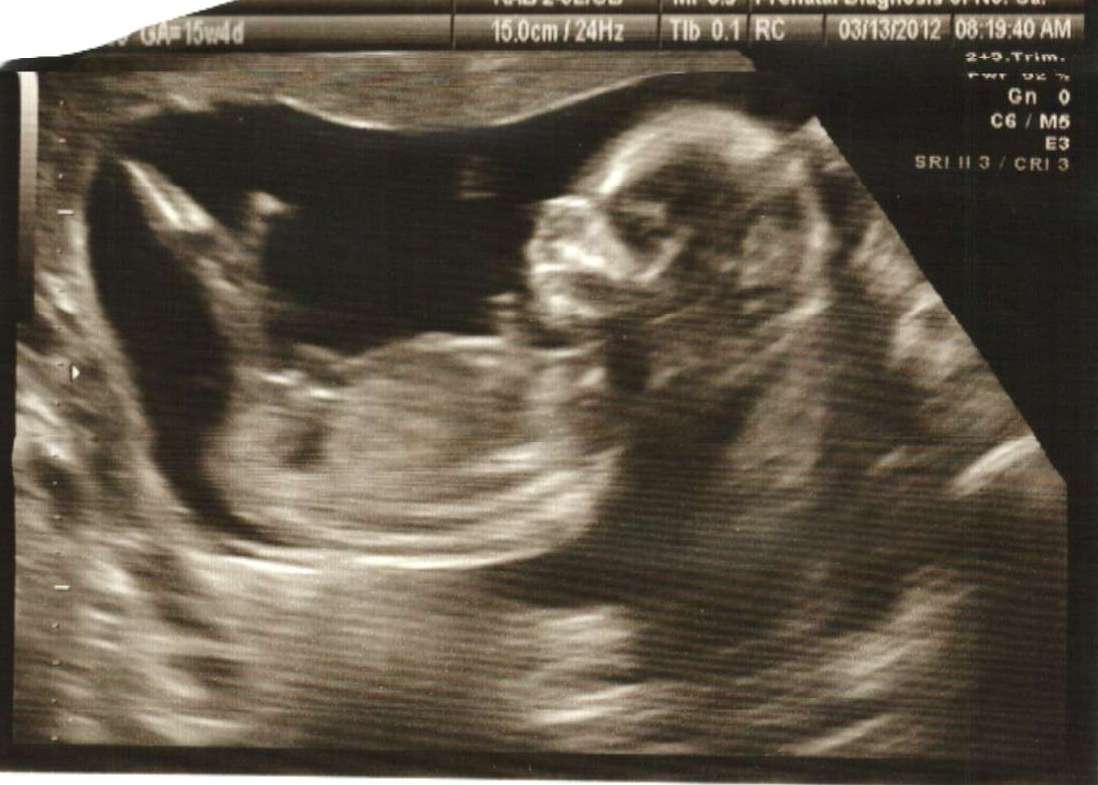

Pls help..........Is it Boy or Girl (clear nub shot) ? Ultrasound (15w4d)

Hi All, Please help us to predict our baby's gender. We had attached ultrasound at the age of 15w4d. But, our OB was not sure to tell the gender of baby. As per her this is too early to tell. The baby's weight is 118g and heart beat is 156. (The picture taken between the two legs of baby) Please tell us.

Do you see any clue in pic 2 and 3 ?

Im going to say Boy